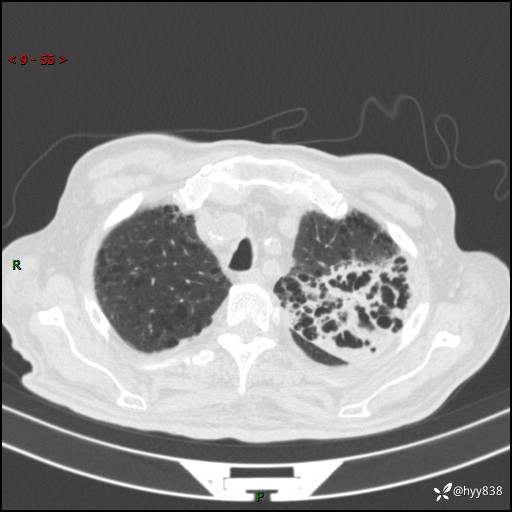

老年男性,间断咳嗽咳痰20余年,加重伴发热1天。呼吸科疑难病例讨论---结果公布

主诉:间断咳嗽咳痰20余年,加重伴发热1天

简要病史:家属代诉患者于20余年前无明显诱因出现咳嗽咳痰,痰为白色泡沫状,未行特殊治疗,不伴胸痛、胸闷、气喘、咳血等不适,1天前上午患者无明显出现发热,查体温39℃,伴咳嗽,咳痰无力,自行予以物理降温对症治疗,今晨2点左右再次出现发热,体温达40℃,自行服用复方氨酚烷胺对症治疗,凌晨3点左右复测体温38.2℃,现患者为求进一步诊治于今日就诊于我院门诊,行胸部CT提示双肺感染,遂以“肺部感染”收入我科。 患者本次起病来精神、食欲、睡眠欠佳,体力下降,体重无明显变化。

辅助检查:CT

胸部CT平扫